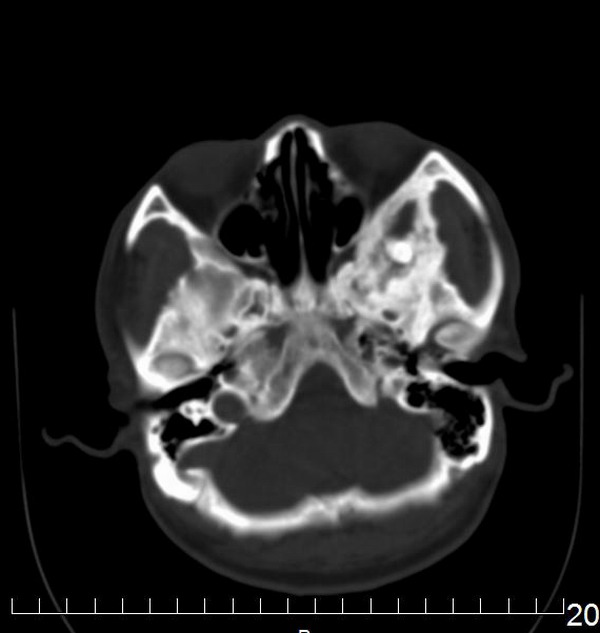

男,56y,自觉左上颌部不适,有时可闻及腥臭鼻涕味。

支持左额骨水平部、蝶骨大翼、颧骨骨纤。

支持左额骨水平部、蝶骨大翼、颧骨骨纤

骨纤维异常增殖症与骨化性纤维瘤(纤维骨瘤)鉴别,确诊需病理。

支持左额骨水平部,蝶骨大翼,颧骨 骨纤维异常增殖症